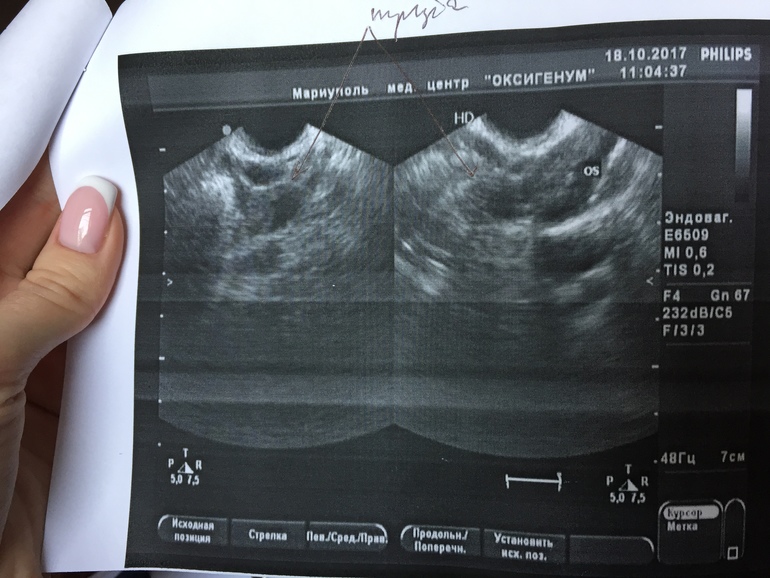

Девчонки,подскажите,что это может быть.Узистка так и не сказала внятно,склоняется к аднекситу в левой трубе.А может это просто фолликул?иоможет кто то сталкивался с таким.

«Рядом с левым яичником виз-ся образование,с утолщенным контуром,просвет жидкостный.ф 19*14мм.а может это внематочная,уже думаю о самом страшном((фото узи

Нет,не беспокоило в принципе.Отслеживаю Овуляцию(фолликулометрия)

Она написала возле яичника.и сказала,немного труба расширена,но почему то не написала об этом..вообщем все странно это

Тоже сразу подумала о том, что врач видит расширенную трубу. ХГЧ не назначили , возможно, так как фаза цикла совершенно не подходит. Но я бы и аднексит не ставила. Либо сальпингит, либо гидросапинкс.